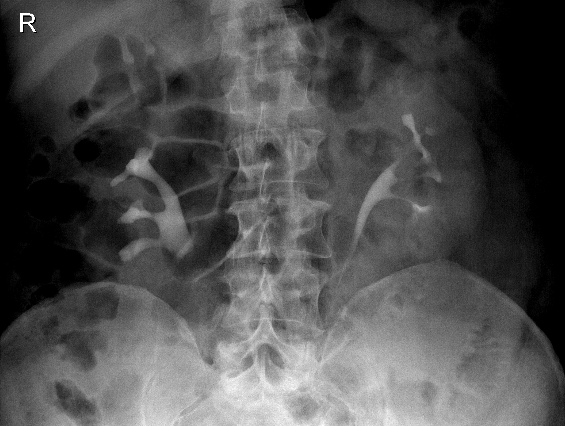

КТ ретроперитонеального фиброза: Изображения и диагностика